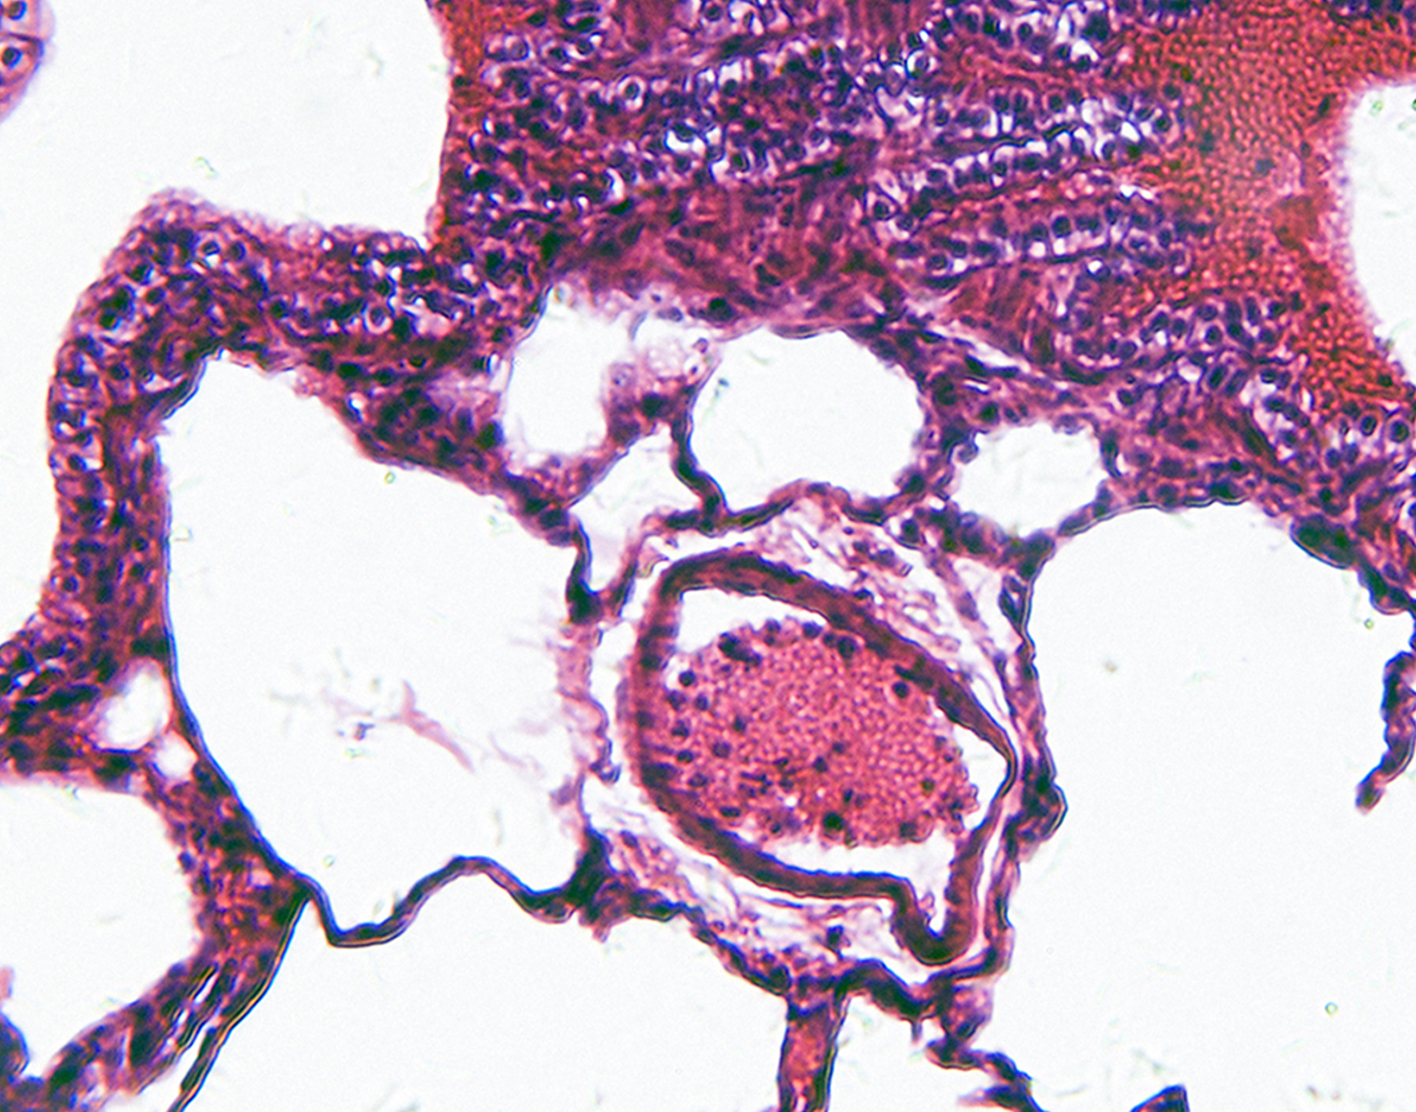

Bronchoscopic culture is a laboratory exam to check a piece of tissue or fluid from the lungs for infection-causing germs.

The sample is sent to a laboratory. There, it is placed in a special dish (culture). It is then watched to see if bacteria or other disease-causing germs grow. Treatment is based on the results of the culture.

Abnormal culture results usually indicate a respiratory infection. The infection may be caused by bacteria, viruses, parasites, mycobacteria, or fungi. The results of the culture will help determine the best treatment.